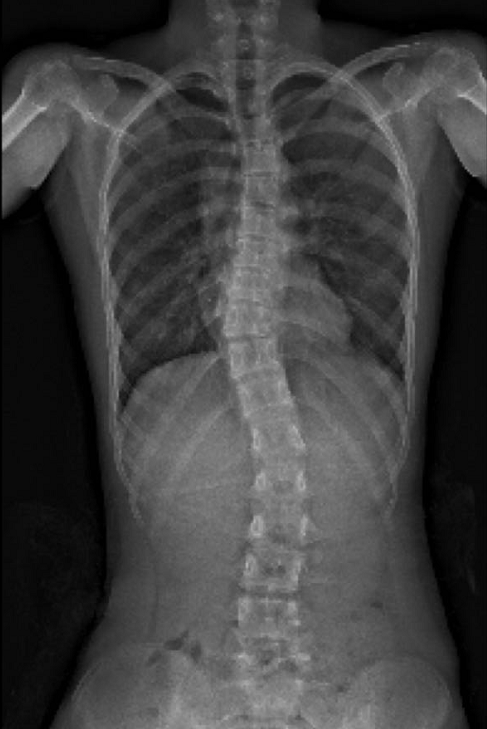

一张X光片胜过千言万语

经过数月的努力,我们再次拍摄X光片。结果令人振奋——变化清晰可见!

说明:惊人改善!侧弯角度(Cobb角)明显缩小,脊柱排列显著优化。

具体改善包括:

– 脊柱侧弯Cobb角明显下降(主要评估指标)

– 双肩、骨盆更加水平对称

– 外观体态显著提升,自信与身体感知力增强

– 整体运动功能大幅改善